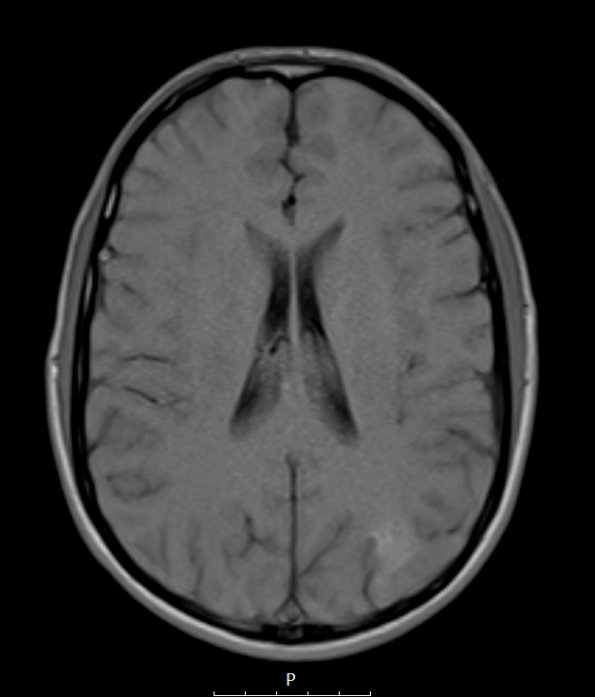

2A2,3 The lesion shows minimal intensity in this T1-weighted scan without (2A2) and with (2A3) contrast.